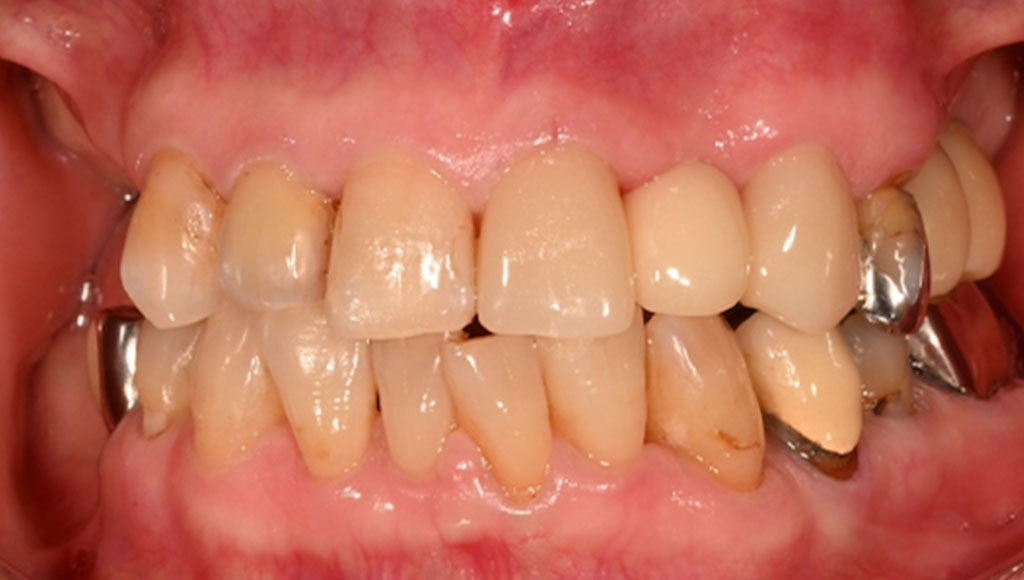

前歯(右123番)ジルコニアブリッジによる審美治療

Before

After

セットしたジルコニアブリッジ

患者様の主訴

70代女性。横浜市在住。右上123番のブリッジが脱離し、ブリッジが合わないため、ジルコニアかインプラントにするか迷い、来院。

診断結果

ジルコニアブリッジを装着するために元のブリッジを外し、歯の形成を行いジルコニアブリッジをセット

治療内容

ジルコニアブリッジを装着するために元のブリッジを外し、歯の形成を行い光学印象(プライムスキャンによる)型取りを行いました。光学印象のデータを元に当院の院内技工室にてデジタル加工を行い、ジルコニアブリッジを作成し、セットを行いました。

治療期間

2回

治療費用

総額:330,000円(税込)

◼️内訳

ジルコニアクラウン:110,000円(税込)/1本×3本

光学印象(プライムスキャン)

リスク・副作用

補綴物の脱落・欠落、咬合違和感、色調補正